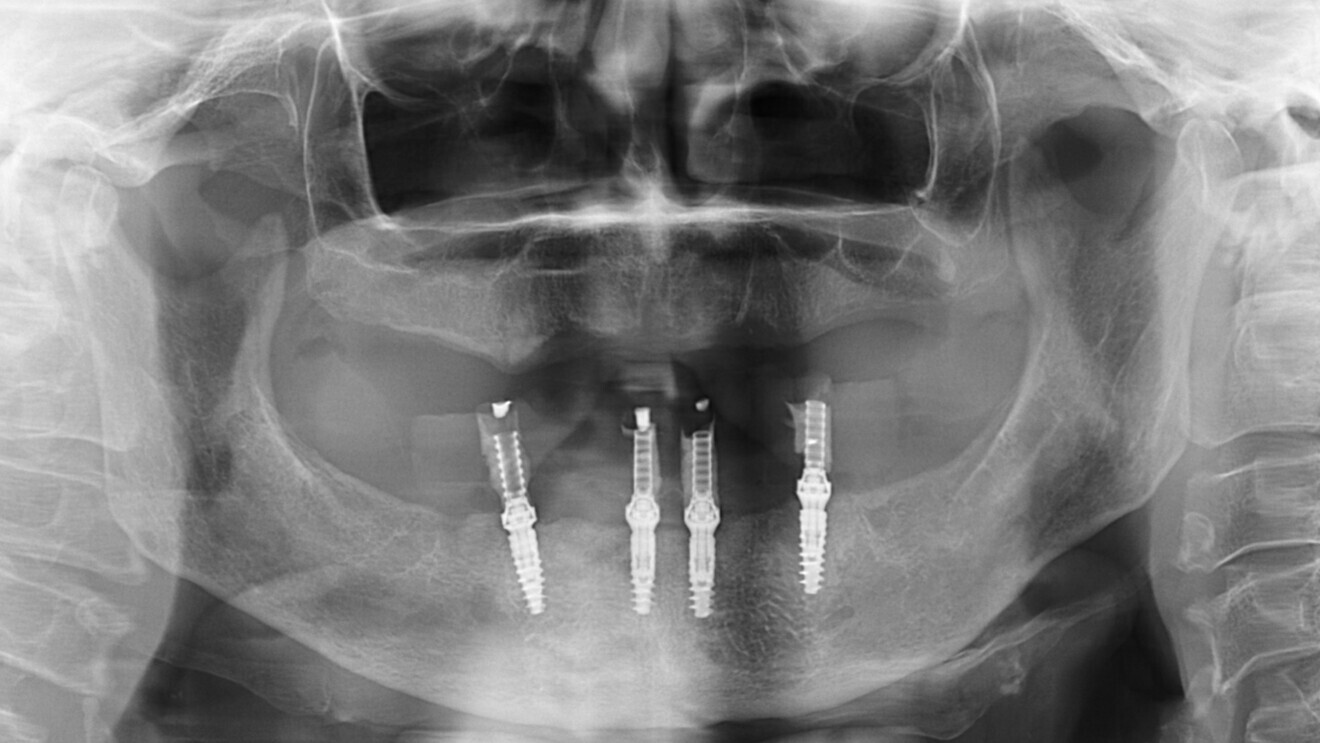

Fig. 3 : Orthopantomogramme de la situation clinique.

Fig. 14 : Contrôle radiologique après mise en place de la prothèse provisoire.